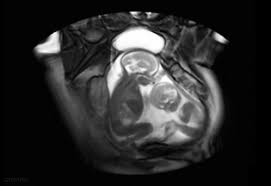

Dr Nabielek Ultraschallbilder 3d Ultraschall

Dr Nabielek Ultraschallbilder 3d Ultraschall from le-cdn.website-editor.net